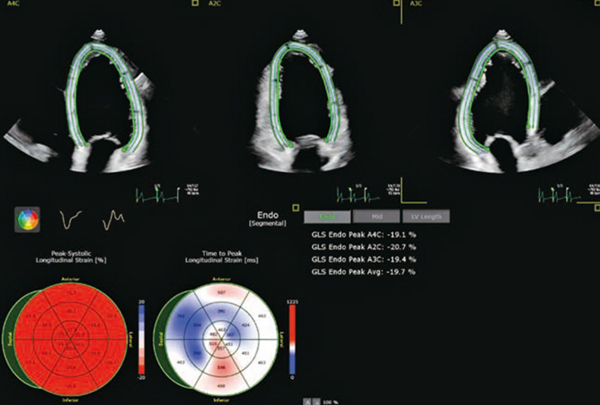

Smart View Selectは,AIがacquireごとに画像を認識し,global longitudinal strain(GLS)解析に適正な画像を層別する。つまり,2D Auto LVのボタンを押すだけで,適正な3断面が選ばれ,GLSとSimpson EFが自動で算出される(図1)。

図1 2D Auto LV with Smart View Select

適正な画像の選択,断面の設定,ROIの設定,GLS解析結果まで自動で実行される。